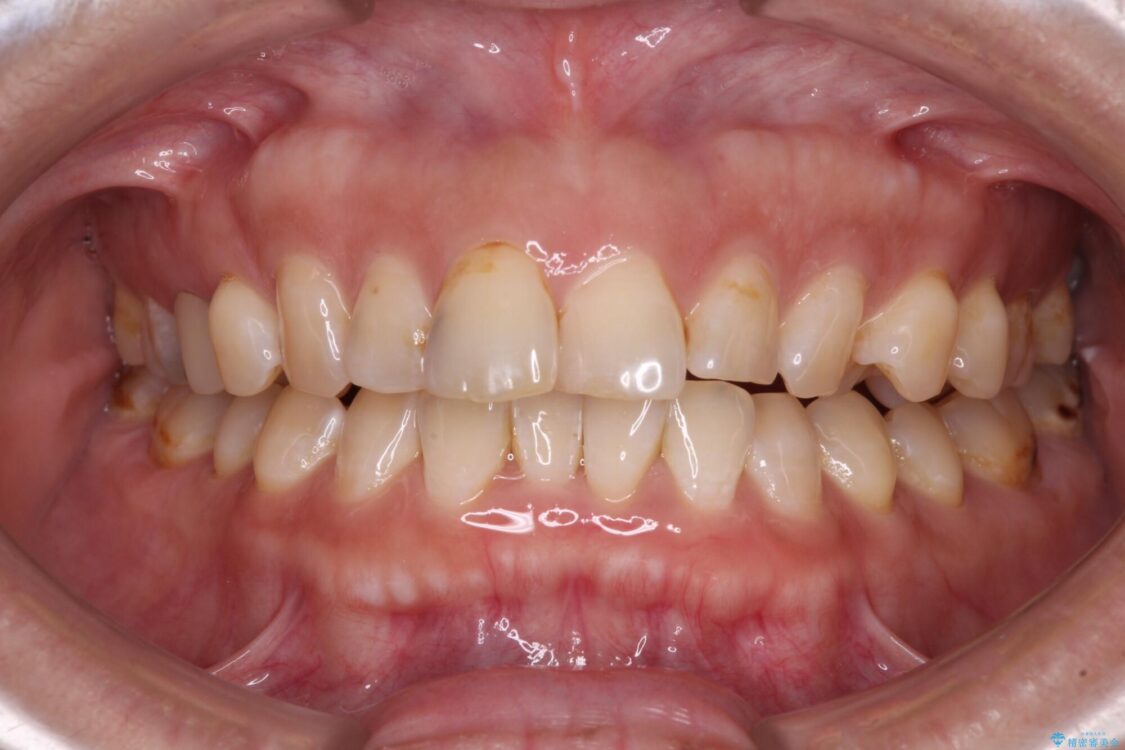

飛び出た上の前歯を気にして来院された患者様です。

奥歯の咬み合わせは、上顎歯列が理想的な一よりも数mm前方にある状態でした。

治療前

• 【モニター】飛び出た前歯を整えたい ワイヤー矯正治療 治療前画像